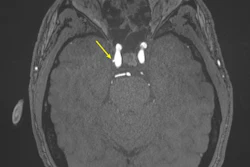

Post-neoadjuvant chemotherapy (NAC) MRI scans in a 66-year-old woman with invasive breast cancer show a lesion that appears fragmented in the first postcontrast axial T1-weighted image (arrow in A) but becomes more conspicuous and homogeneous in the last delayed phase (arrow in B). Despite these visual differences, response classification was identical between abbreviated and full diagnostic MRI. Pathologic analysis confirmed a partial response with residual invasive carcinoma.RSNA